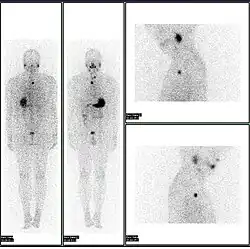

A nuclear medicine whole body bone scan. The nuclear medicine whole body bone scan is generally used in evaluations of various bone-related pathology, such as for bone pain, stress fracture, nonmalignant bone lesions, bone infections, or the spread of cancer to the bone. -

A nuclear medicine parathyroid scan demonstrates a parathyroid adenoma adjacent to the left inferior pole of the thyroid gland. The above study was performed with Technetium-Sestamibi (1st column) and iodine-123 (2nd column) simultaneous imaging and the subtraction technique (3rd column). -